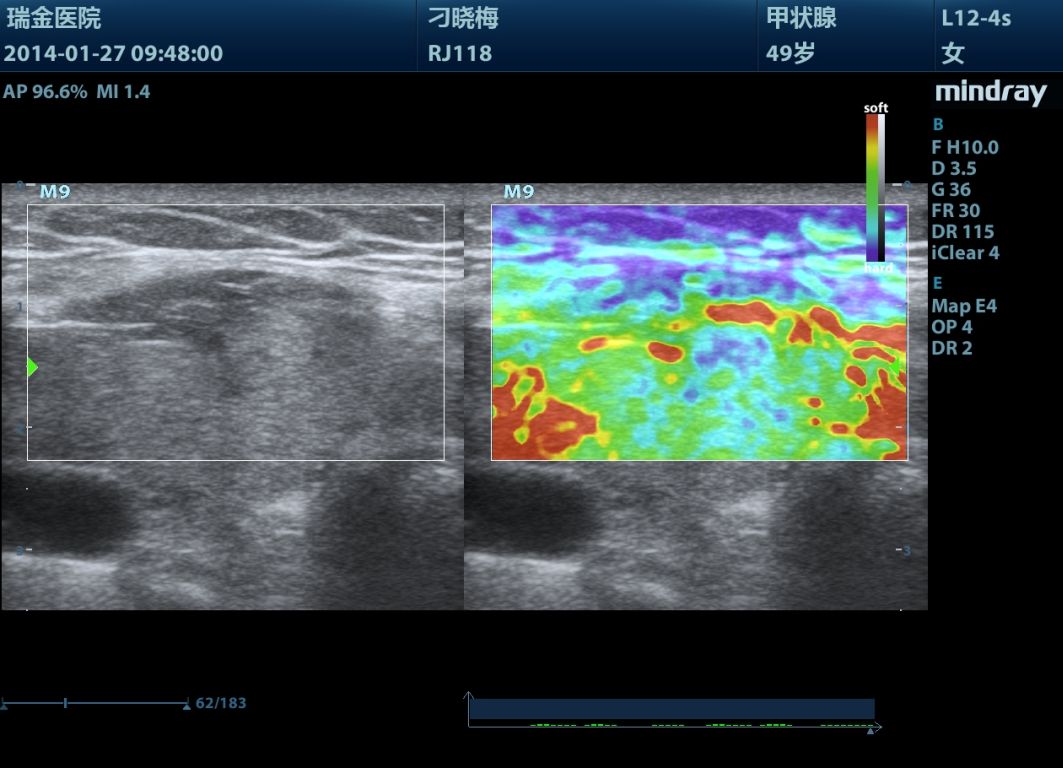

Mindray M9 je dopplerovský ultra ľahký prenosný UZV prístroj najvyššej High End triedy s použitím single crystal 3T sond (vynikajúce zobrazenie blízkeho i vzdialeného poľa), HDR FLOW, ECHO BOOST, Natural Touch Elastography, kontrastného zobrazenia, TDI. Špeciál hlavne pre kardiológiu.

Klinické obrázky: